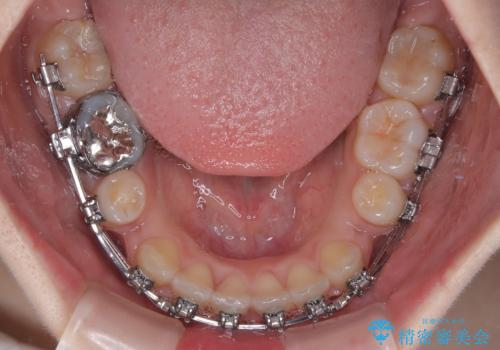

- 矯正装置

- メタルブラケット

- 治療計画

- 前歯のクロスバイトと口元の膨らんだ横顔の印象を気にして来院された患者様です。

レントゲン写真の分析結果からは、それほど口元が突出しているという結果にはなりませんでした。

しかしながら、唇を閉じたときに口元に緊張感があり、そのまま叢生を解消すると横顔が突出した印象になる可能性が高かったため、上下左右の小臼歯4本を抜歯して、ワイヤー装置にて矯正治療を行うこととしました。